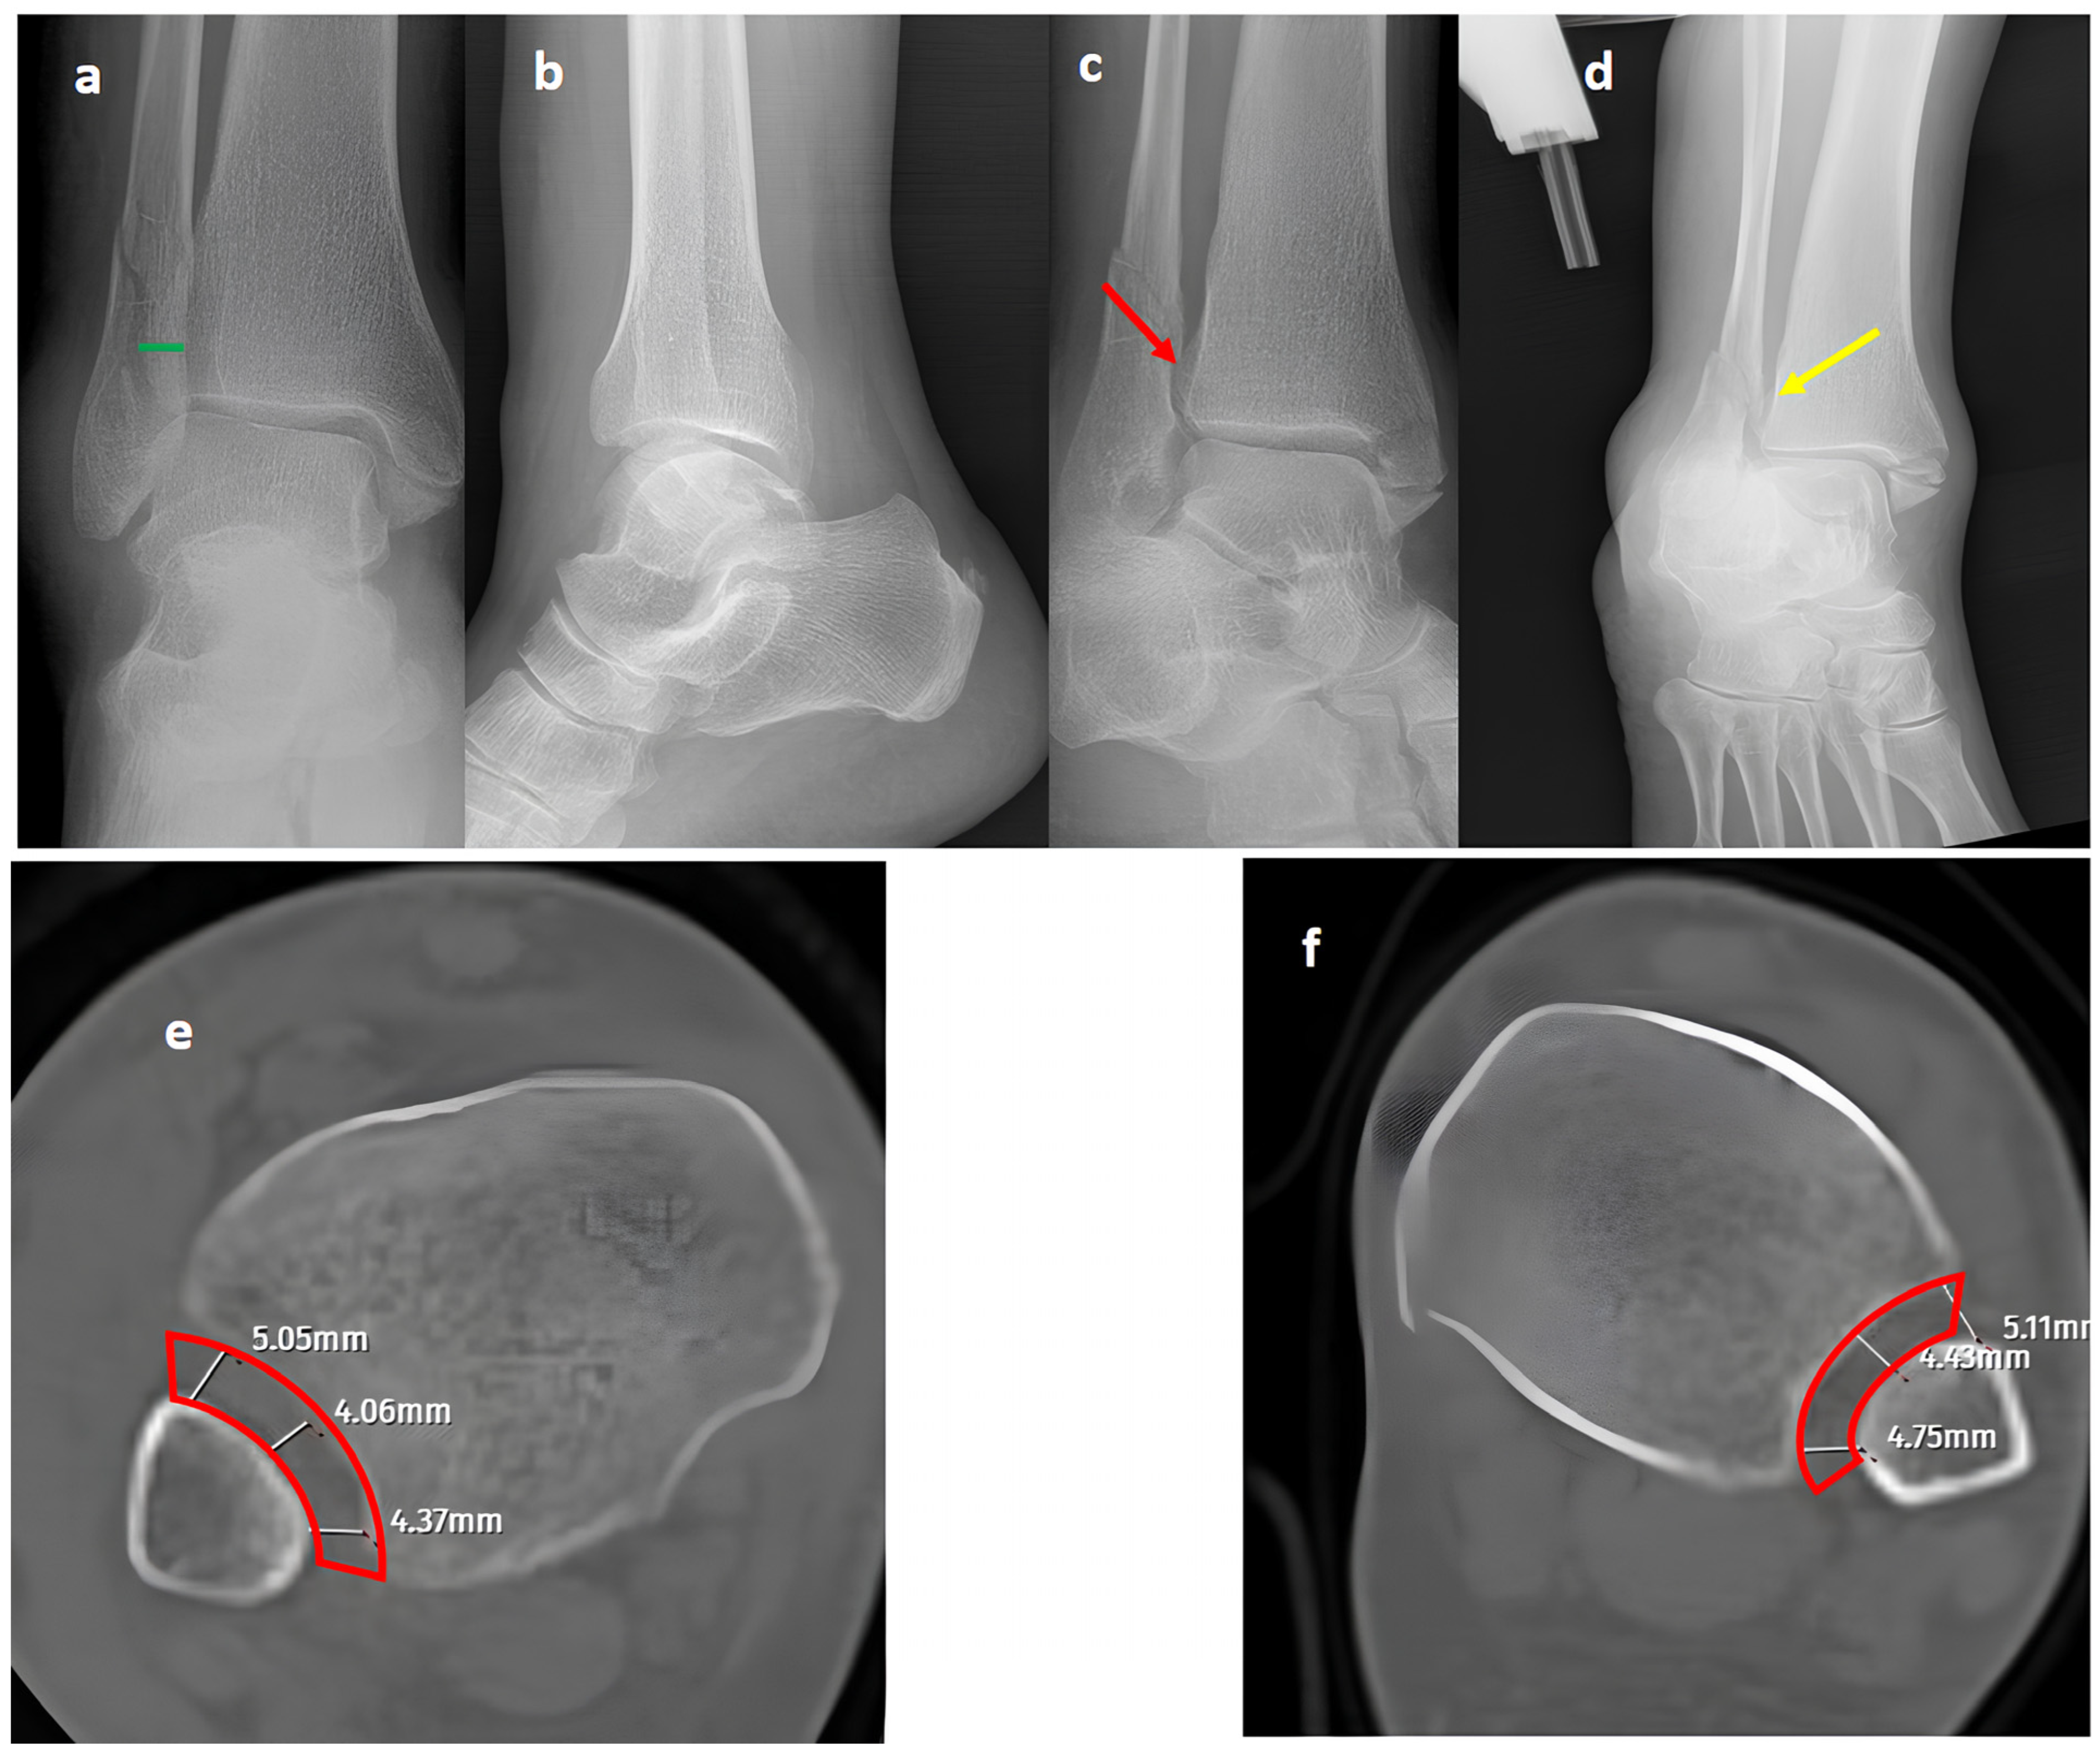

Figure 1.

A trimalleolar right ankle fracture. (a,b) Standard AP and lateral views showing a bimalleolar fracture with a normal distal tibiofibular overlap (green line). (c) A mortise view showing an open distal tibiofibular distance (red arrow) indicating syndesmosis injury. (d) A GAASA view showing lateral displacement of the talus with a shift in the medial malleolus and distal fragment of the fibular segment. However, the proximal segment of the fibula is in place, indicating that the proximal syndesmosis is intact (yellow arrow). Axial CT images of the injured right ankle (e) and the uninjured left ankle (f) show measurement of the tibiofibular space (red block bow), which appears similar and within normal ranges, indicating an intact syndesmosis.

In our series, 19 of 36 SER type II and IV cases did not involve syndesmotic injury (Figure 1), which is consistent with the idea that medial and lateral injuries must be carefully assessed before surgical stabilization. These findings highlight that GAASA imaging is particularly reliable in PER injuries, where all medial and lateral structures are disrupted and the fibula is extensively fractured. In such cases, gravitational force causes the talus to exert downward pressure on the distal fibular fragment, producing clear widening of the medial clear space and distal tibiofibular joint [28]. Maisonneuve injuries, not classified by the Lauge-Hansen system, are inherently unstable and require surgical syndesmosis stabilization [29]. In our study, three cases had clear distal tibiofibular widening without pathological medial clear space widening (Figure 2). This contrasts with the cadaveric study by Krahnebühl et al., which reported that stress radiographs are reliable only when deltoid and syndesmotic injuries coexist, but are ineffective for isolated syndesmosis injuries [5]. Our findings suggest that even when the medial malleolus and deltoid ligament remain intact, gravitational force alone can cause lateral fibular displacement, resulting in decreased tibiofibular overlap.